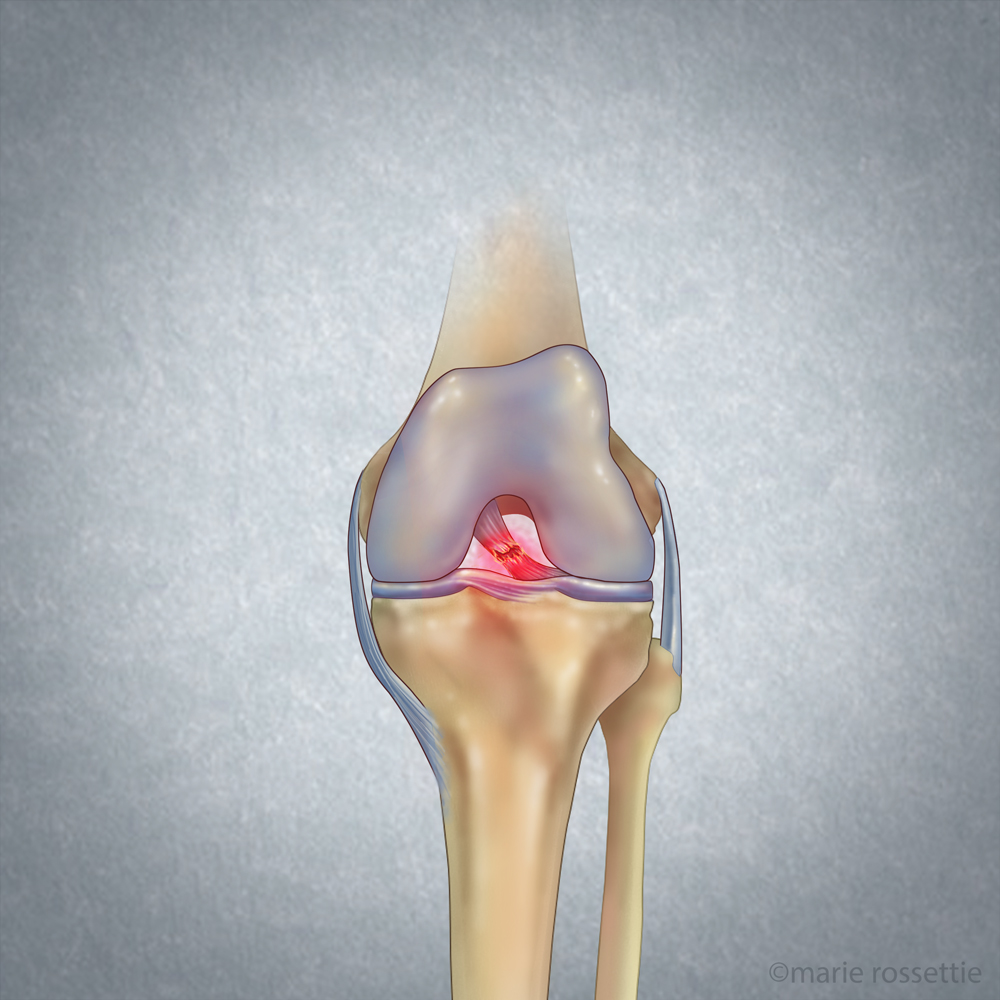

Lamar suffered by video analysis what looked to be a PCL sprain. The PCL is an internal ligament that helps to stabilize the knee. When his left knee was driven into the ground this past weekend he most likely sprained this structure.